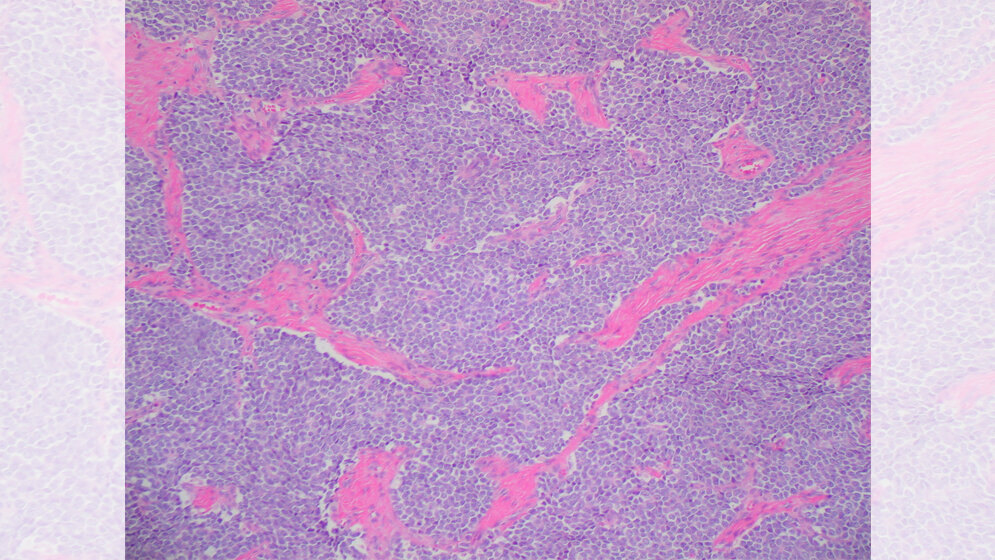

In Heidelberg beschäftigen sich Wissenschaftler sehr intensiv mit dem Ewing-Sarkom: Sie untersuchen die Rolle eines charakteristischen „Krebsgens“, das dazu führt, dass sich die Tumorzellen sehr schnell und fast fehlerfrei vermehren. Mit Hemmstoffen wollen sie gegensteuern und Tumorzellen letztlich zur Selbstzerstörung bringen. Die Deutsche Krebshilfe fördert das Projekt mit 233.000 Euro. „Sarkome sind die dritthäufigste Krebsart im Kindes- und Jugendalter. Im Vergleich zu anderen Krebsarten haben die jungen Patienten eine deutlich schlechtere Chance auf Heilung“, sagt Professor Dr. Dr. Thomas Grünewald, Leiter der Forschungsgruppe Translationale Pädiatrische Sarkomforschung am Hopp-Kindertumorzentrum Heidelberg (KiTZ) und Leiter der gleichnamigen Abteilung am Deutschen Krebsforschungszentrum (DKFZ). Beim Ewing-Sarkom liegt die Sterblichkeitsrate noch immer bei etwa 30 Prozent. Gemeinsam mit seinem Team möchte Grünewald neue Behandlungsmöglichkeiten für diesen bösartigen Knochentumor entwickeln.

Die Wissenschaftler/-innen konzentrieren sich dabei auf eine Veränderung des Erbgutes, die bei fast allen Ewing-Sarkomen vorkommt. Mehrere Gene sind dabei zu einem „Krebsgen“ verschmolzen – mit schwerwiegenden Folgen: Das neu gebildete Gen bringt Chaos in die Regulation der Zellteilung und löst damit das Tumorwachstum aus. „Beim Ewing-Sarkom teilen sich die Zellen besonders schnell“, erklärt KiTZ-Wissenschaftlerin Dr. Florencia Cidre-Aranaz, die das Projekt leitet. Normalerweise häufen Zellen, die sich sehr schnell teilen, beim Kopieren ihres Erbgutes viele Fehler an. Der Körper merkt dann, dass mit den Zellen etwas nicht stimmt und sorgt dafür, dass sie absterben. „Beim Ewing-Sarkom passieren aber erstaunlicherweise kaum Fehler“, erläutert Cidre-Aranaz.